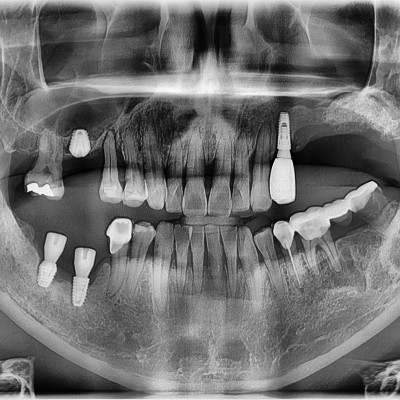

임플란트 재수술 #16.46.47 타원임플란트 제거 후 임플란트 재수술 + 치조골 이식술 시행하였습니다.

임플란트 재수술 #36,37 기존 타원 임플란트 제거 후 뼈이식 임플란트 동시식립

임플란트 재수술 #25.26.27 타원 임플란트 제거 후 임플란트와 치조골 이식 후 시행하였습니다.

임플란트 재수술 #37 타원 임플란트 제거 후 임플란트와 치조골 이식술 같이 시행하였습니다.

임플란트 재수술 #46.47 임플란트가 제거된 상태로 내원 하셨고 추후 재식립 후 보철물까지 부착하였습니다.